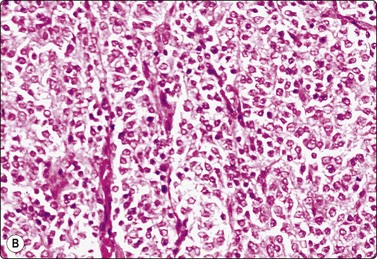

Seminoma (Figs 13.30 and 13.31)14,50,57-63,65,66

image image

Fig. 13.30 Seminoma

(A) Dispersed cells with large pale nuclei and poorly defined cytoplasm; note ‘tigroid’ background, smudged nuclei and small lymphocytes (MGG, HP); (B) Dispersed cells; moderately pleomorphic vesicular nuclei; single or multiple prominent nucleoli; many scattered lymphocytes (Pap, HP).

image

Fig. 13.31 Mediastinal seminoma

Smear from large mediastinal mass clinically thought to be thymic carcinoma. Cluster of poorly cohesive, obviously malignant cells and some necrotic debris. Cytoplasmic vacuolation and nuclear fragility suggest malignant germ cell tumor; some lymphocytes present but specific typing not possible. Histology confirmed seminoma (MGG, HP).

Criteria for diagnosis

Cell-rich smears,

Dispersed cells, little tendency to clustering,

Highly fragile cytoplasm and nuclei (’tigroid background’ (TB) and nuclear trailing),

Large rounded vesicular nuclei; distinct nucleoli, smaller than in embryonal carcinoma,

Irregular chromatin with some clearing,

Abundant fragile, pale/clear cytoplasm; some marginal vacuoles (punched-out vacuoles),

Lymphocytes, plasma cells,

Tangled chromatin threads (seminoma cells and lymphocytes),

Some epithelioid histiocytes, epithelioid granulomas (variable),

Striking contrast in size between seminoma cells and the background of lymphocytes and plasma cells.

Immunocytochemistry: cells positive for PLAP, c-kit (CD117) and OCT 3/4, and negative for CD30, AE1/AE3, and CK7, CK8, CK18 and CK19, although focal pancytokeratin-positive cells may be seen.

Seminoma is a highly cellular neoplasm of poorly cohesive cells and little stroma. The presence of a lace-like tigroid background (TB), and the high cellularity including lymphocytes account for the intense navy-blue color of the smears. This may suggest the diagnosis even before microscopic study. Comments about the origin of TB and the distinction from ‘lymphoglandular bodies’ have been made elsewhere.60 TB may go unnoticed in Pap-stained smears, but is more conspicuous in DQ smears (Fig. 13.30). A diagnosis of seminoma should not be based solely on the presence of TB or TB-like material. We have observed TB-like material also in aspirates of embryonal carcinoma. The contrary is also true: seminoma should not be ruled out simply because the pathologist is unable to identify TB.14 Large seminomas may show prominent necrosis. Necrosis is a major cause of false negatives in testicular FNA.59 Tumor giant cells or syncytiotrophoblastic cells may be seen in aspirates of seminoma, but can also be found in embryonal carcinoma, mixed TGCT and in trophoblastic tumors.

The plasmatic membrane is well-defined in seminoma, but it is difficult to see in embryonal carcinoma. When lymphocytes, plasma cells, histiocytes and epithelioid granulomas are abundant and seminoma cells scarce, a diagnosis of granulomatous orchitis may be entertained: the absence of spermatozoids and of the germinal line suggest a seminoma.60

Chromatin trailing may be prominent, particularly if the sample was smeared vigorously. This artifact has no diagnostic value in itself, since it may occur also in embryonal carcinoma, yolk sac tumors, lymphomas and acute orchitis. When the smear is dominated by this artifact, and there are no acute inflammatory cells and no spermatogenesis, the pathologist must search carefully for preserved diagnostic cells. In this situation, a tentative diagnosis of seminoma may be made.14

Lymphocytes, plasma cells and even ‘lymphoglandular bodies’ may be prominent in smears of seminoma and may lead to an erroneous diagnosis of lymphoma. Lymphoblasts may also be mistaken for seminoma cells.

Familiarity with the cytology of testicular seminoma helps in the recognition of extragonadal seminoma and metastatic seminomas (Fig. 13.31). Immunostaining may be of help in doubtful cases.69